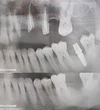

Periimplantitis

Peri-İmplant Mukozitis

Implant tedavisi